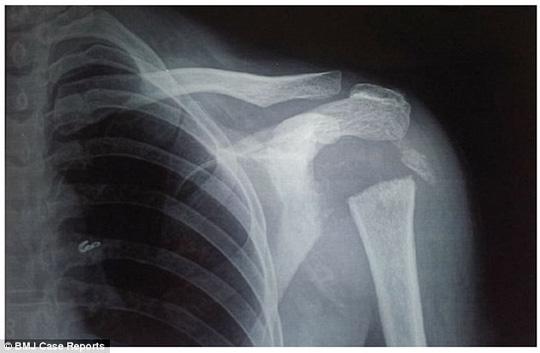

Các bác sĩ tại Viện Khoa học Y tế Pondicherry đã chụp X-quang phần vai và tay người phụ nữ. Họ cũng "hết hồn" khi phát hiện phần đáng lẽ tồn tại một khớp nối giữa xương cánh tay và vai hoàn toàn trống không. Người phụ nữ hoàn toàn không gặp chấn thương nào trước đó. Chỉ đơn giản là xương của cô đã bốc hơi một cách bí ẩn!

Tác giả chính của bài báo - Bác sĩ Pasupathy Palaniappan cho biết người phụ nữ mắc một căn bệnh lạ gọi là Gorham-Stout, hay "bệnh xương biến mất". Căn bệnh khiến cơ thể tự "ăn" dần các xương của bệnh nhân. Trên phim X-quang có thể thấy các xương này từ từ trong suốt rồi biến mất hoàn toàn.

Tấm phim X-quang lạ lùng của nữ bệnh nhân - ảnh: BMJ Case Reports